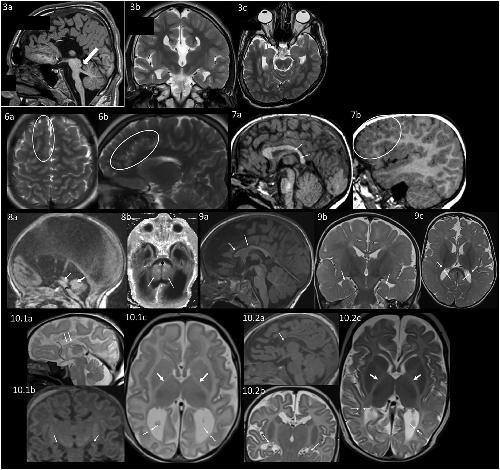

Figure 2. Neuroanatomical differences appreciated on brain MRI

MRI of individual 3. 3a: Sagittal T1 weighted image shows complete absence of the corpus callosum, a hypoplastic pons and a prominent superior cerebellar peduncle (arrow). 3b: Coronal T2 weighted image also shows an absent corpus callosum. 3c: Axial T2 weighted image shows left plagiocephaly.

MRI of individual 6 at an unknown age. 6a: Axial T2 Blade showing increased gyral folding in the frontal lobes (circle). 6b: Sagittal T2 Blade showing increased gyral folding in the parasagittal frontal lobe (circle).

MRI of individual 7 at 2 years. 7a: Sagittal 3D FLASH in the midline showing small posterior body and splenium of the corpus callosum (arrows). 7b: Sagittal 3D FLASH of the right hemisphere showing increased gyral folding in the frontal lobes (circle).

MRI of individual 8 as an infant. 8a: Sagittal T1 showing hypoplastic pons (∗), aqueductal stenosis (thin arrow), and small vermis (thick arrow). 8b: Axial inversion recovery T1 showing hypoplastic pons (∗) and small cerebellar hemispheres (arrowheads).

MRI of individual 9 at 11 months. 9a: Sagittal MPRAGE shows thin corpus callosum, particularly the anterior body and genu (arrows). 9b: Coronal T2 TSE with incompletely rotated hippocampi (arrows). 9c: Axial T2 TSE showing delayed myelination (myelination should be seen in the gyri throughout the posterior temporal and occipital lobe and decreased white matter volume shown by arrows).

MRI of individual 10.1 as a neonate. 10.1a: Sagittal T2 showing hypoplastic thin corpus callosum (arrows). 10.1b: Coronal reformation of sagittal MPGR showing small incompletely rotated hippocampi (arrows). 10.1c: Axial T2 showing lack of myelin in the posterior limb internal capsule (thick arrows) and decreased white matter volume (thin arrows).

MRI of individual 10.2 as a neonate. 10.2a: Sagittal MPGR showing hypoplastic thin corpus callosum (arrow). 10.2b: Coronal T2 TSE showing small incompletely rotated hippocampi (arrows). 10.2c: Axial T2 TSE showing lack of myelin in the posterior limb internal capsule (thick arrows) and decreased white matter volume (thin arrows).